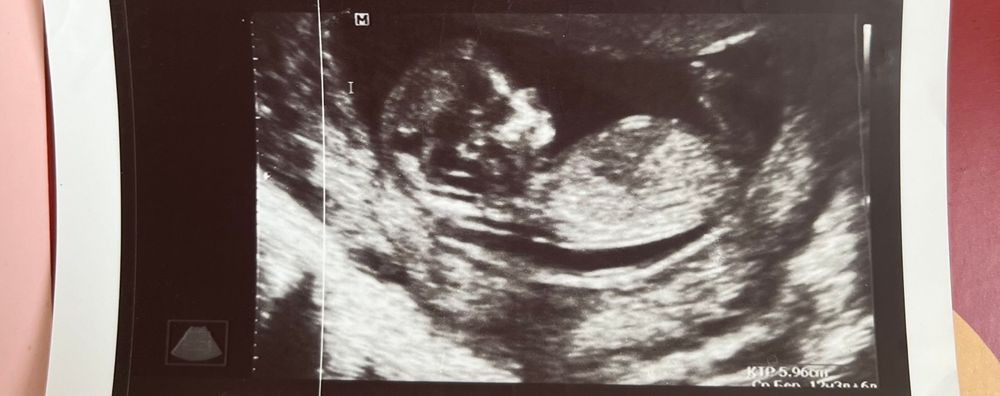

1 фото - узи 12 недель